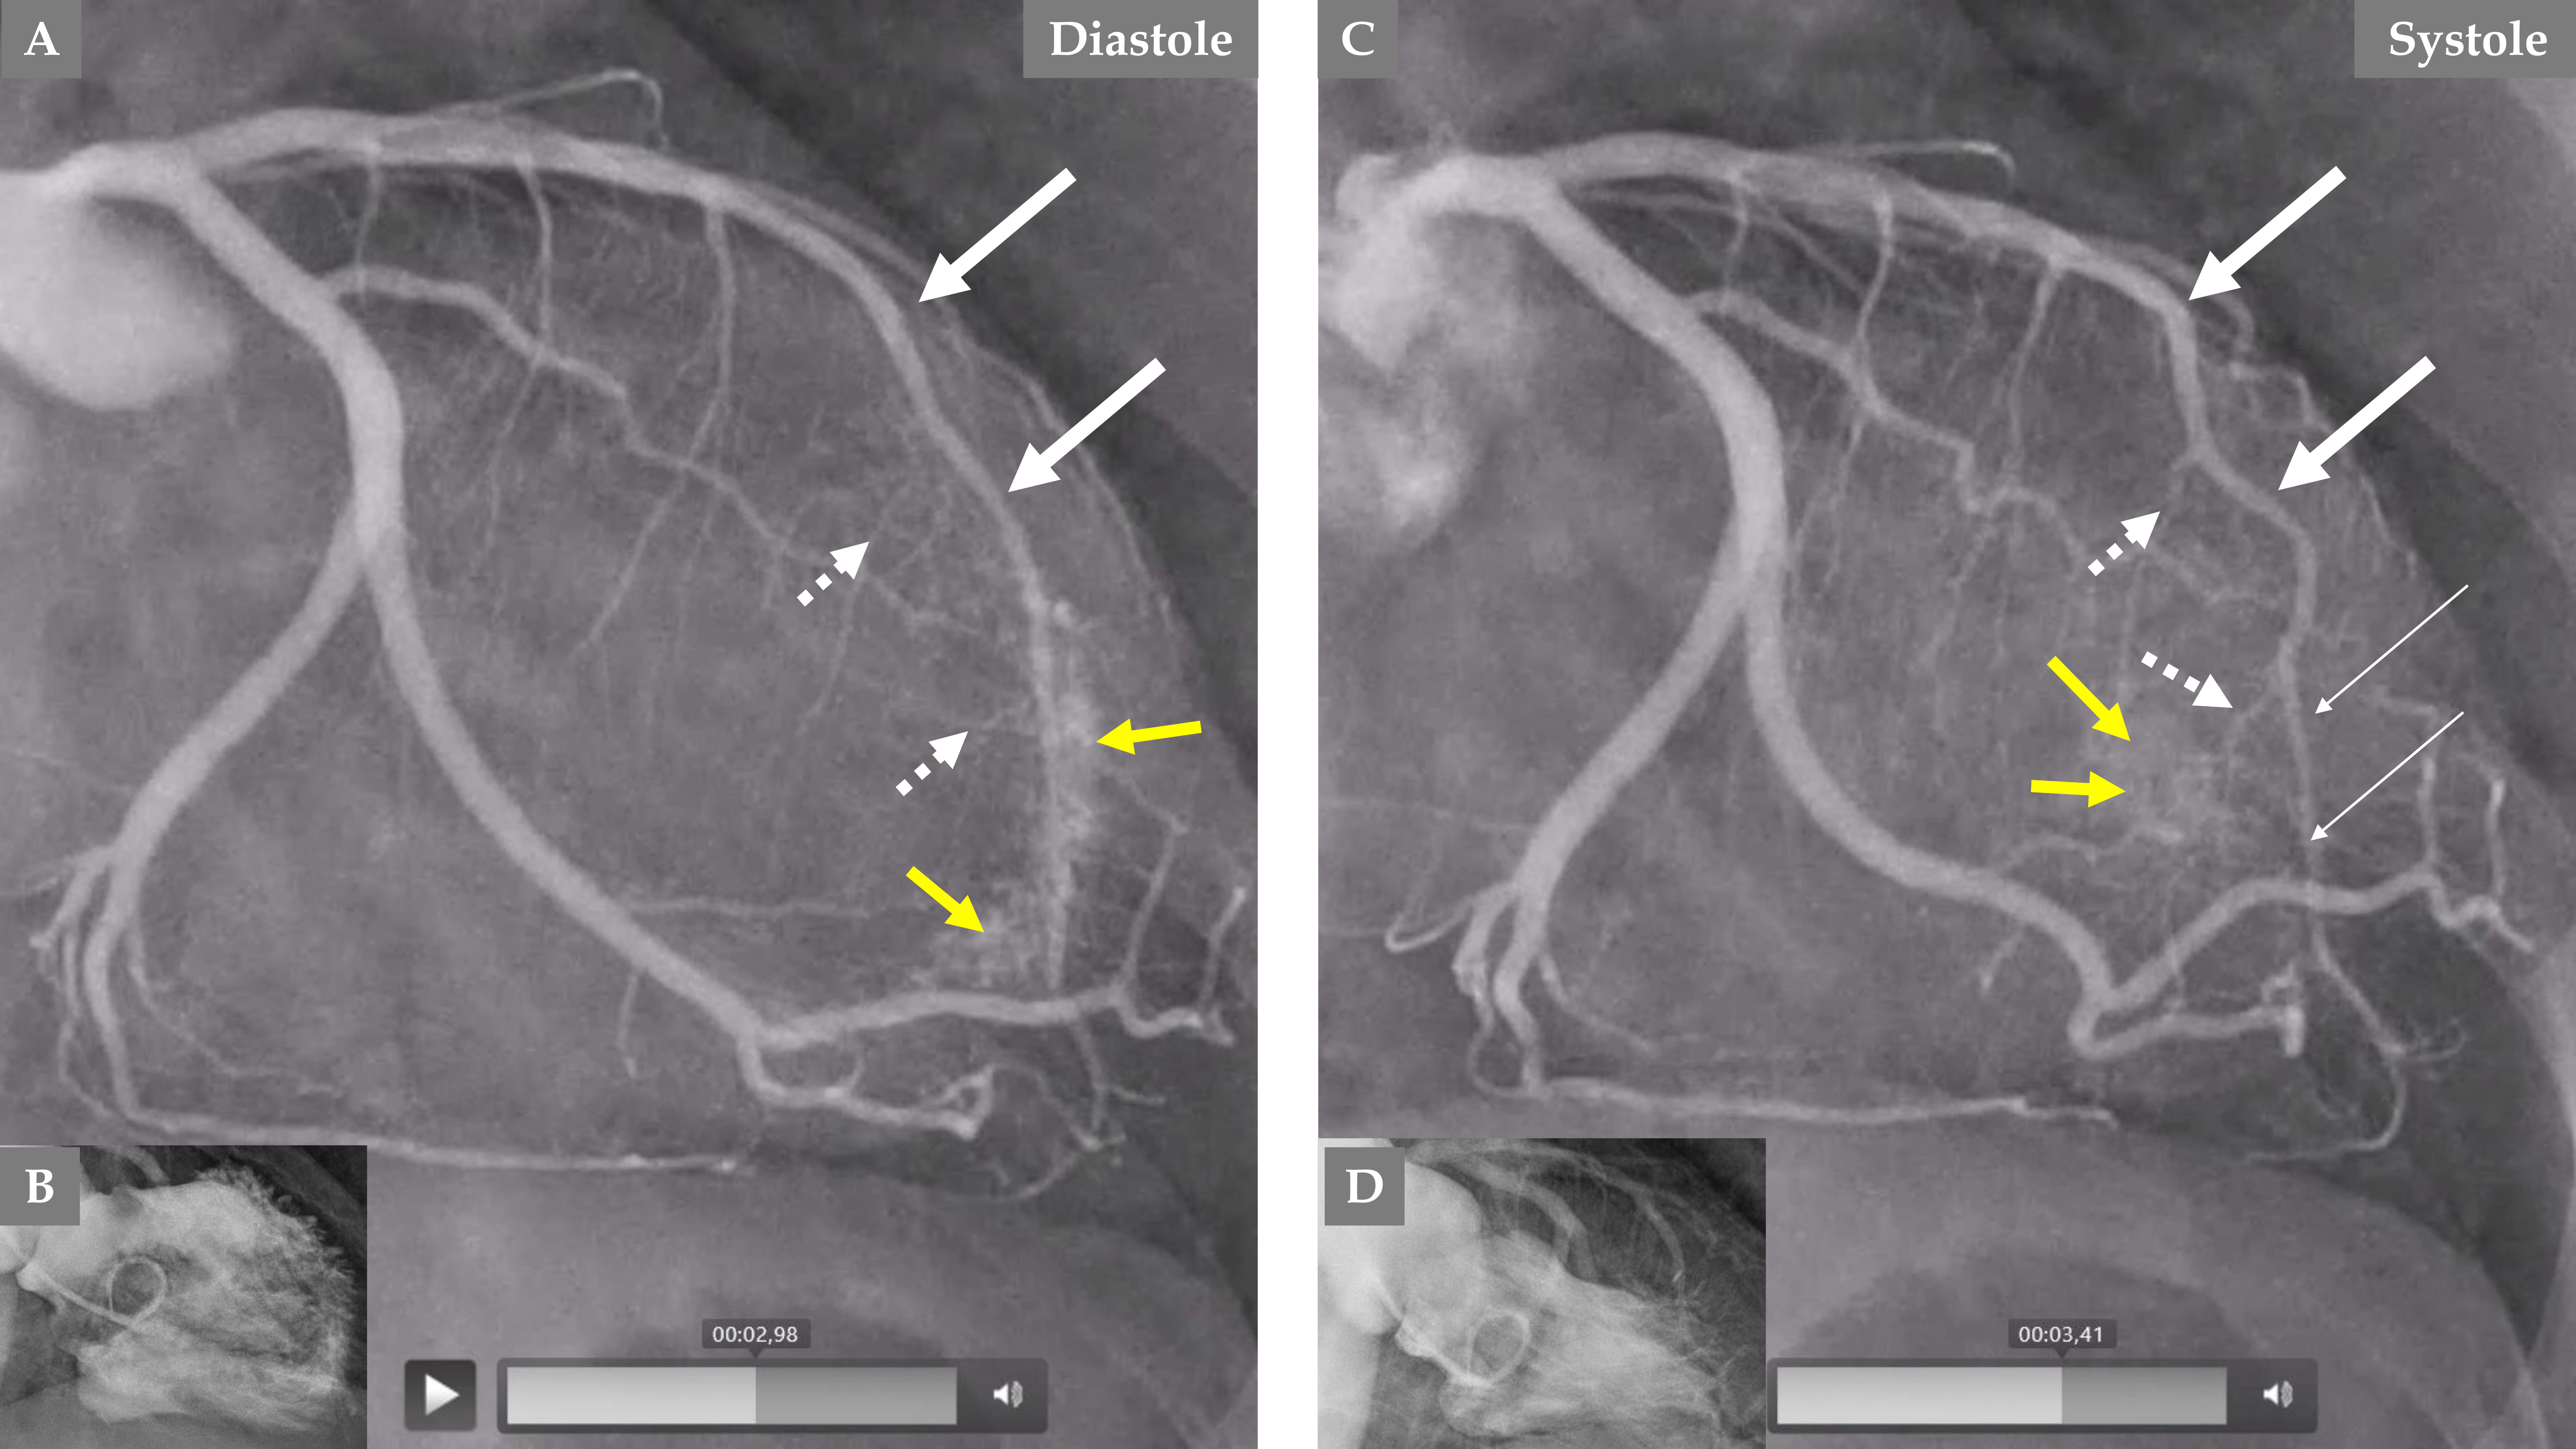

Fig. 5. Comparison of the LCA angiography during the index presentation and follow-up after 5 months. LCA angiography during diastole (A). Contrast left ventriculography during diastole and systole (B). Both (A and B) are during index presentation, where the patient had a clear mid-apical ballooning pattern of TS. LCA angiography during diastole (C). Contrast left ventriculography during diastole and systole (D). Both (C and D) are during the follow-up, 5 months after the index presentation, where there was complete normalization of left ventricular function. The LAD has a normal diameter in the proximal segment and normal three septal branches in both (A and C); meanwhile, the distal two-thirds of the LAD is thin and compressed (A, broken thin long white arrows), and the LAD is almost normal (C, thick long white arrows) during follow-up. The septal branches from the distal two-thirds of the LAD are practically invisible (A, short broken white arrows). The septal branches from the distal two-thirds of the LAD (C, short white arrows) are clearly seen. There are no signs of coronary artery-left ventricular micro-fistulae (CALVMF) during the index presentation (A, yellow question marks). Clear signs of CALVMF are observed around the distal segment of the LAD in the projection; however, CALVMF are most probably from the distal marginal branch (C, yellow arrows) when all projections of LCA angiography have been analyzed. This figure clearly shows that the LAD, the septal branches, and CALVMF were compressed by the myocardial stunning during the index presentation and were relieved during follow-up when the left ventricular function is completely normalized.

An interesting finding, which forms a novel observation, is that no signs of CALVMF was observed during the index presentation with a mid-apical ballooning pattern of TS (Fig. 3C and Fig. 5A); however, during follow-up coronary angiography when the left ventricular dysfunction has completely normalized, there was clear signs of CALVMF, most probably arising from the distal marginal branches (Fig. 4A,C during diastole and systole and Fig. 5C). It is also clearly seen that the contrast staining moves to the left ventricular cavity during systole (Fig. 4C). These micro-fistulae were not visible during index presentation because of the compression by the myocardial stunning (myocardial cramp) caused by TS. The comparison between the index presentation, where there were no signs of CALVMF, and the follow-up 5 months later, where signs of CALVMF appeared clearly, is demonstrated in Fig. 5.